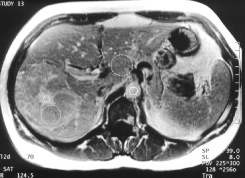

Patiente porteuse d'une HNF typique

La lésion se rehausse franchement à la phase artérielle et redevient iso signal ensuite. La cicatrice est parfaitement visible et se rehausse progressivement . Les mesures de signal confirment parfaitement la dynamique du contraste.